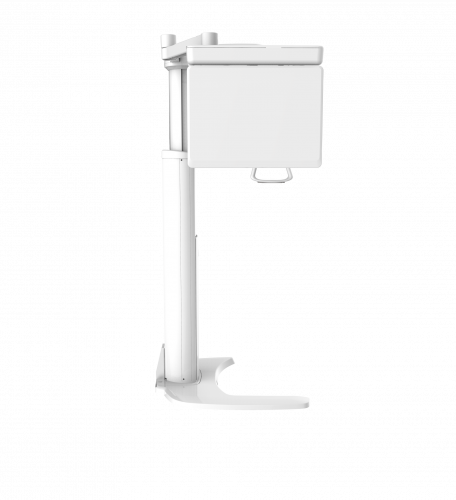

| TYPE | TOP VIEW | FRONT VIEW |

|---|---|---|

|

PaX-i (Pano) |

|

|

|

PaX-i SC (Pano/Scan Ceph) |

|

|